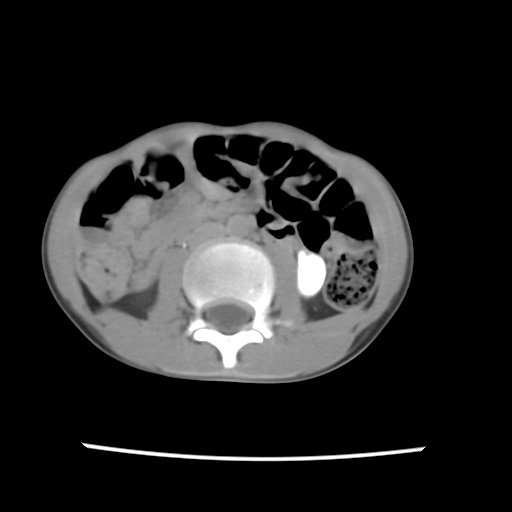

A 07 years old child with left side of abdomen pain

current CT images: